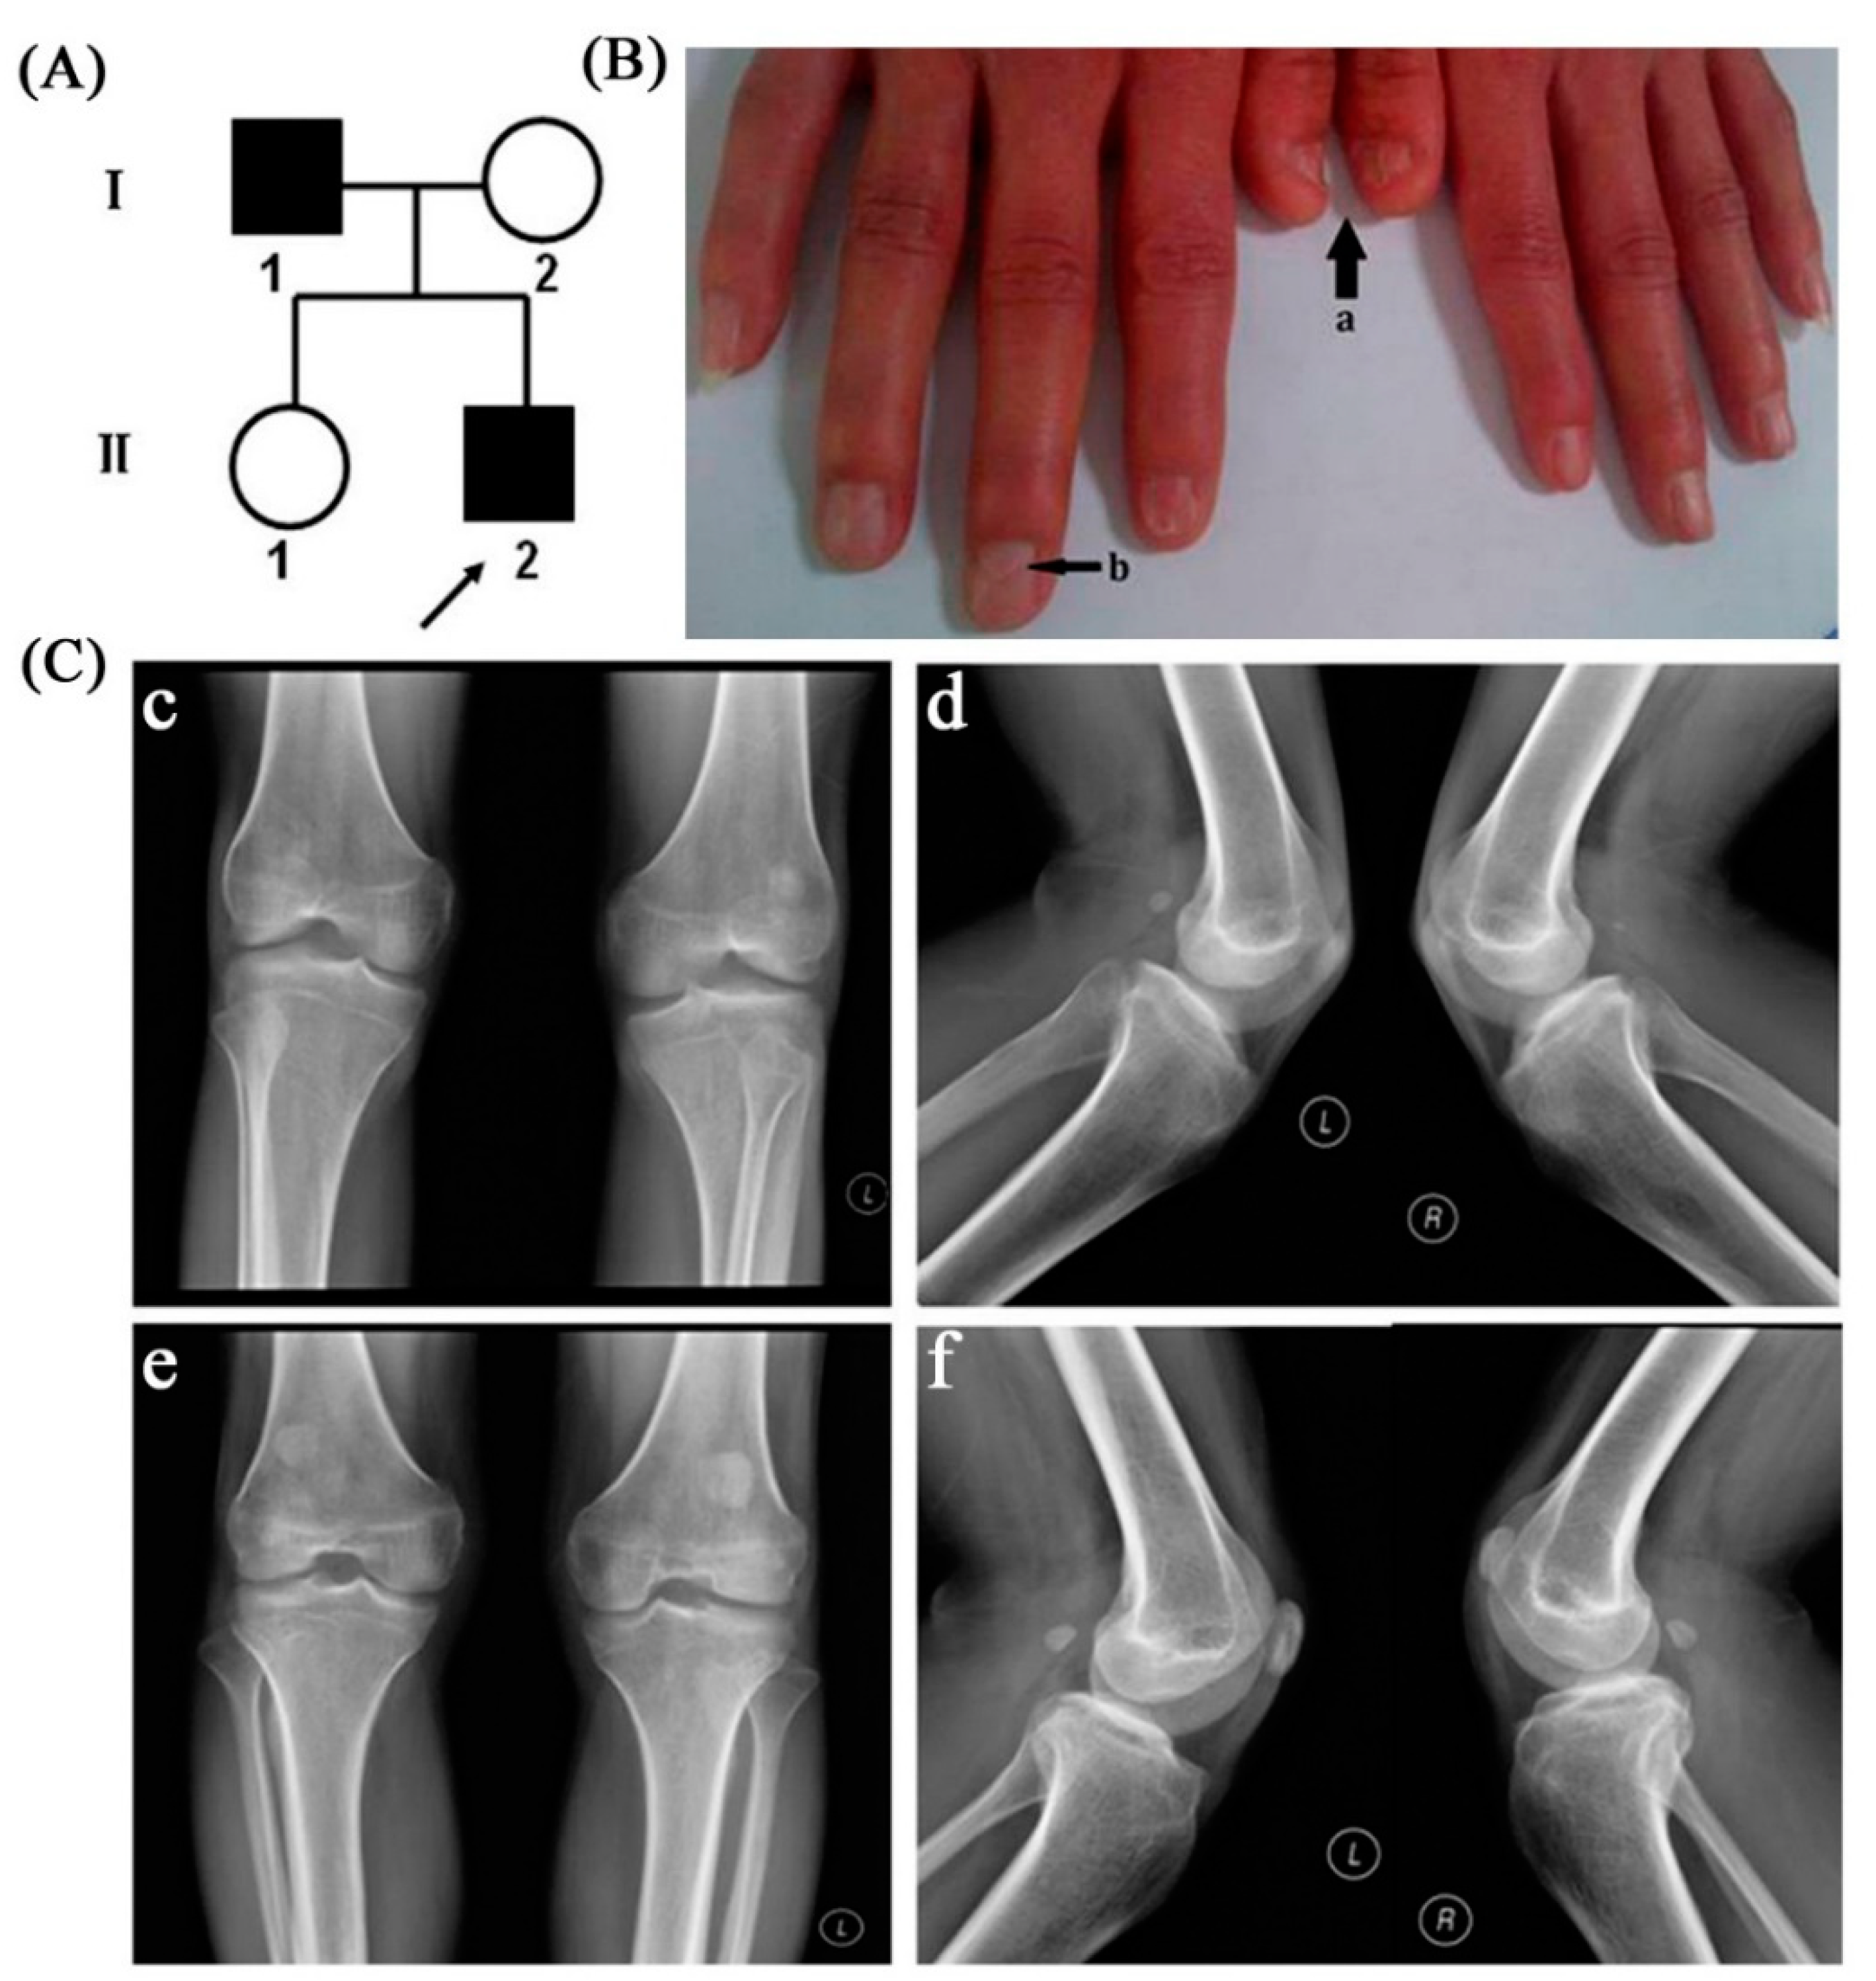

2.1. Clinical Manifestations